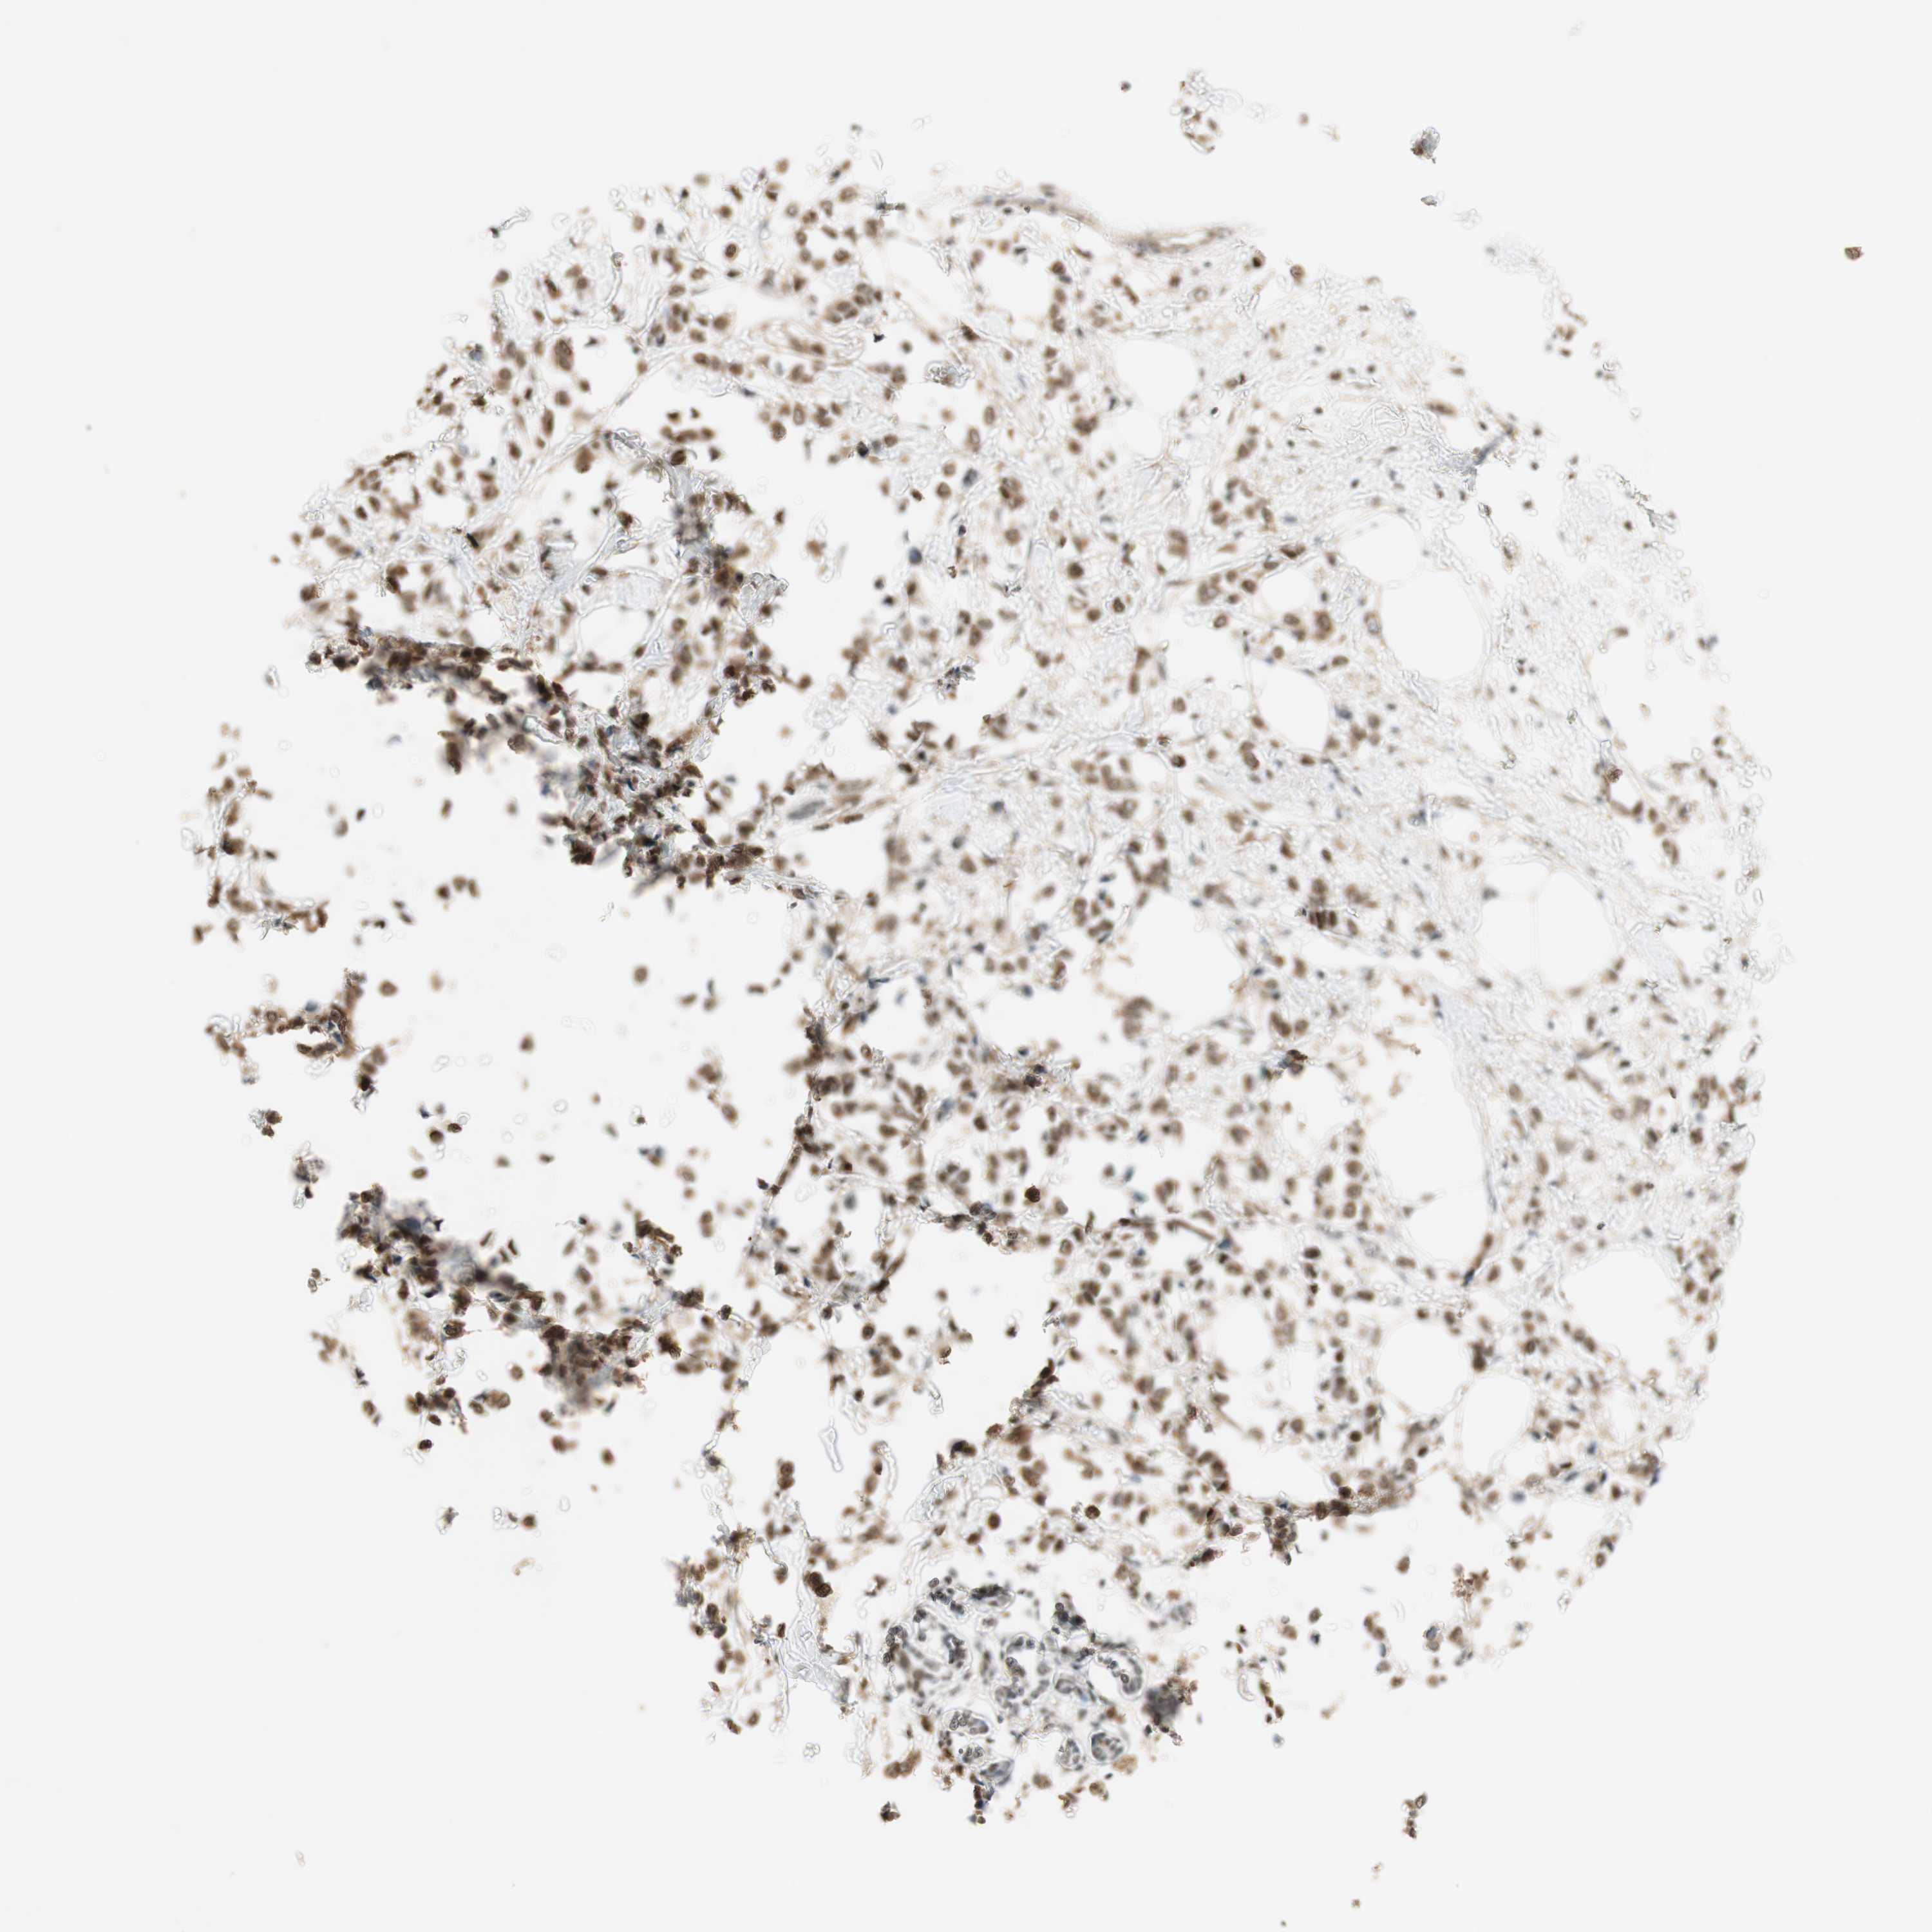

BRCA TCGA BRCA VALIDATION PROTEIN EXPRESSION